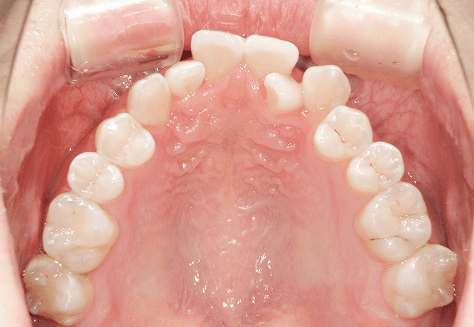

M.H

治療前

治療後

主訴

前歯が出ている。下の歯並びが特に気になる。奥歯でしっかり噛めない。

診断

上顎前突・叢生・シザーズバイト

年齢/性別

20代/男性

抜歯部位

下顎両側大三大臼歯(口腔外科にて)

上顎両側第一小臼歯・下顎左側側切歯

(当院にて5,500円×3) -

使用装置

上下エッジワイズ→インビザライン(PBM使用)

保定装置

上下ビベラリテーナー

料金

初回資料採得・・・・・・・30,000円

診断料・・・・・・・・・・33,000円

動的治療終了時資料採得・・5,500円 -

基本料金

880,000円

診察料金

5,500円×44回

-

治療期間

3年6カ月